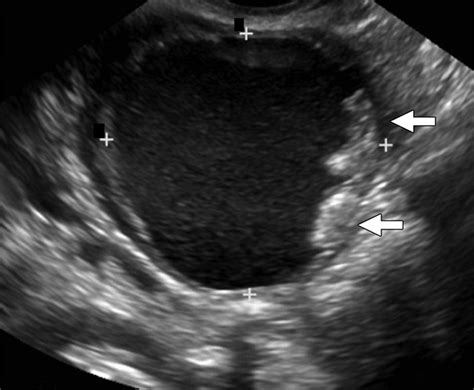

• Solid Components: Fluid-filled cysts are often benign, but solid masses within an ovarian cyst can be more concerning.

• Irregular Borders: A mass with thick, irregular walls or "papillary projections" (small, finger-like growths inside or outside the cyst) is generally viewed with higher suspicion.